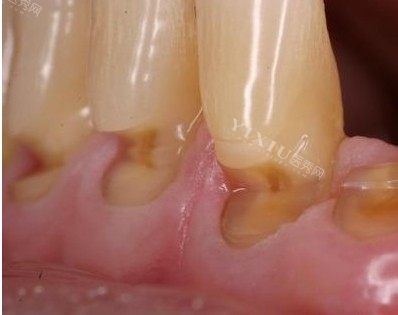

头一阶段的治疗就是治疗牙周病。洗牙的过程并不好受,医生用仪器在我的牙齿上刮来刮去,每一下都让我觉得牙齿酸痛难忍。尤其是刮治的时候,那种深入牙龈的刺痛感,让我差点忍不住要跳起来。我紧紧地握着拳头,眼泪都快流出来了。医生一直在旁边鼓励我:“坚持一下,很快就好了,这是为了你的牙齿健康。”

洗完牙后,我的牙齿变得特别敏感,冷热酸甜都不能碰。医生给我开了一些抗菌漱口水和降低炎症药,让我按时使用,还叮嘱我要改变刷牙方式,使用软毛牙刷,采用巴氏刷牙法。我按照医生的要求,每天小心翼翼地刷牙、漱口,不敢有丝毫懈怠。

在治疗牙周病的这段时间里,我每天都盼着牙龈能快点好起来。每次照镜子,看到红肿的牙龈,心里就充满了焦虑。不过,随着时间的推移,我发现牙龈出血的情况逐渐减少了,红肿也慢慢消退了,这让我看到了一丝希望。